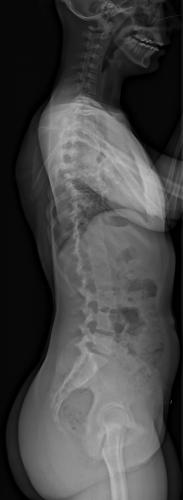

Images de scolioses opérées 16 janvier 202418 janvier 2023 par Damien Scoliose Thoracique 1 Radiographie pré-opératoire de Face Radiographie pré-opératoire de Profil Radiographie de Face à 3 mois post-opératoire Radiographie de Profil à 3 mois post-opératoire